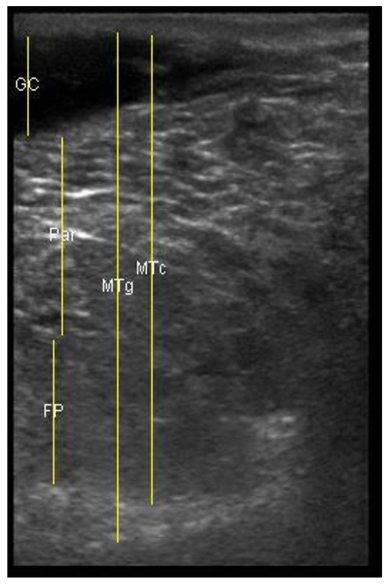

The image processing was undertaken using ImageJ software [28] as used by Abràmoff et al. [29]. The scales between pixels and millimetres were calculated based on the number of pixels, the scanning depth (mm), and the transducer width (mm) (Figure 4). This method relies on the ability of the operator to interpret and identify lines on the images. To standardize the assessment compartment depth, drawing templates were created for each time point as used by Molenaar et al. [30] and included four representative images from four different yearling ewes with and without the lines drawn for each compartment (Appendix A). The total depth of mammary gland conservative (MTc) was the smallest likely demarcation (abdominal wall) of the mammary gland (Figure 5a), and total depth of the mammary gland generous (MTg) was the largest likely demarcation of the mammary gland visible on the image [30] (Figure 5a). The MTc, MTg, fat pad (FP), parenchyma (PAR), and gland cistern (GC) depths were estimated at the deepest point for each sub-compartment, excluding the skin layers, using the straight tracer (Figure 5a) and were expressed in millimetres.

Figure 5.

(a) Demonstration of delimitations of the mammary total depth conservative (MTc) and generous (MTg), mammary gland cistern (GC), parenchyma (PAR) and the fat pad (FP) and (b) Demonstration of randomly positioning of regions of interest (1, 2, 3) in the parenchyma.